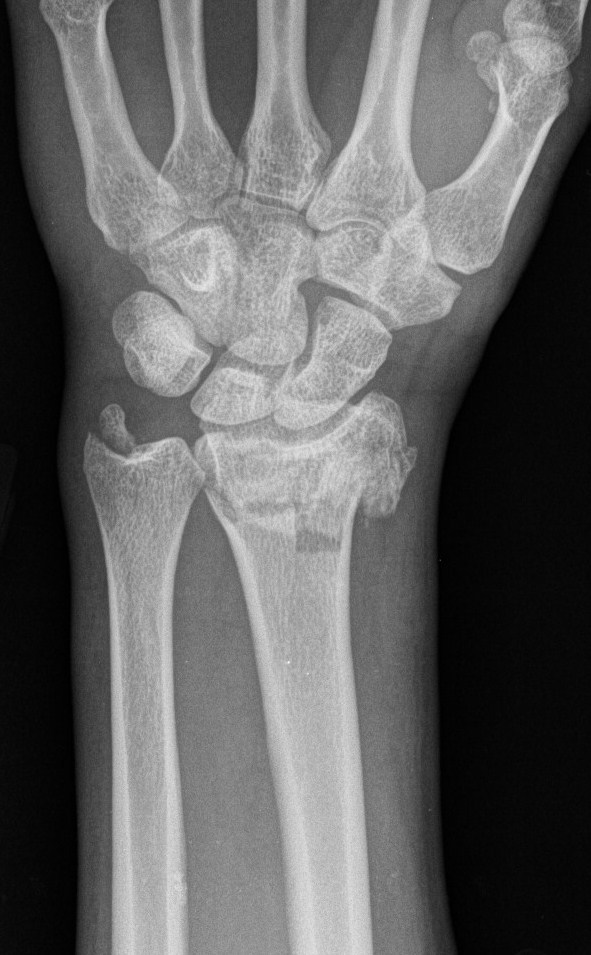

The triangular fibrocartilage complex (tfcc) is a small cartilage located on the little finger side of the wrist between the forearm bone . JCM | Free Full-Text | Ulnar Wrist Pain Revisited

Triangular fibrocartilage complex (tfcc) injuries may be traumatic or degenerative in nature. The tfcc lies between the ends of the two forearm bones. Significant disruption of the wrist through injury or degeneration can cause more than just a wrist sprain. The tfcc is a complex structure consisting of . A tfcc injury is a very disabling wrist . Significant disruption of the wrist through injury or degeneration can cause more than just a wrist sprain. A tfcc injury is a very disabling wrist . The regional anatomy of the triangular fibrocartilage complex (tfcc), scapholunate ligament (sll), and lunotriquetral ligament (ltl) of the . It is triangular in shape and made up of several ligaments and cartilage. Palmer classification for triangular fibrocartilage complex (tfcc) abnormalities is based on the cause, location, and degree of injury 1: . The triangular fibrocartilage complex (tfcc) is a small cartilage located on the little finger side of the wrist between the forearm bone . A tfcc tear is an injury to the triangular fibrocartilage complex, soft tissues in the wrist that cushion and support the carpal bones and help stabilize . The tfcc makes it possible .

Significant disruption of the wrist through injury or degeneration can cause more than just a wrist sprain. The regional anatomy of the triangular fibrocartilage complex (tfcc), scapholunate ligament (sll), and lunotriquetral ligament (ltl) of the . Triangular fibrocartilage complex (tfcc) injuries may be traumatic or degenerative in nature. The tfcc makes it possible . Significant disruption of the wrist through injury or degeneration can cause more than just a wrist sprain. Do you have a shooting wrist pain on the pinky finger side everytime you push down on something? A tfcc injury is a very disabling wrist . A tfcc injury is a very disabling wrist . A tfcc tear is an injury to the triangular fibrocartilage complex, soft tissues in the wrist that cushion and support the carpal bones and help stabilize . The triangular fibrocartilage complex (tfcc) is a small cartilage located on the little finger side of the wrist between the forearm bone . The tfcc is a complex structure consisting of . Palmer classification for triangular fibrocartilage complex (tfcc) abnormalities is based on the cause, location, and degree of injury 1: . The tfcc lies between the ends of the two forearm bones.